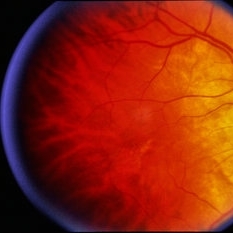

Age Related Macular Degeneration

Age Related Macular Degeneration

Mar 29 2013 by Henry J. Kaplan, MD

Geographic atrophy with small hemorrhages due to subretinal neovascular membrane development.

Condition/keywords: choroidal neovascularization (CNV), geographic atrophy